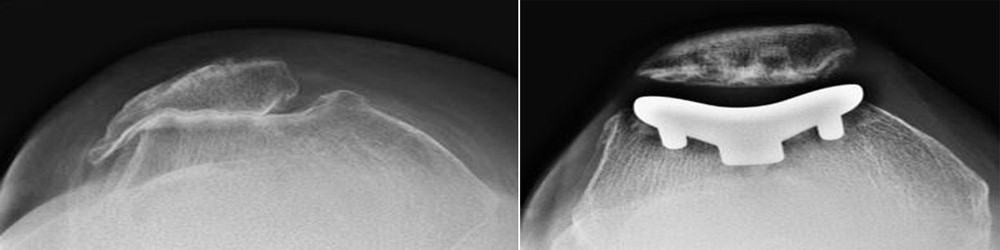

X-rays of knee before and after patellofemoral replacement

(Left) This X-ray is taken from above the knee. The patella and the trochlear groove of the femur have become deformed due to osteoarthritis. There is now bone rubbing on bone. (Right) The same knee after patellofemoral replacement. The patellar implant on the underside of the kneecap does not show in an X-ray.